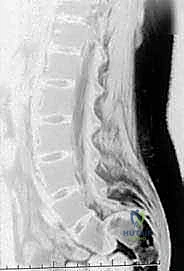

هي الخطوة الأولى والأساسية. يتم التقاط صور للعمود الفقري من عدة زوايا (أمامية، جانبية، ومائلة). الأشعة الجانبية هي الأهم لتحديد درجة الانزلاق (حسب تصنيف مايردينغ). كما يتم إجراء أشعة ديناميكية (أثناء الانحناء للأمام وللخلف) لتقييم مدى "عدم الاستقرار" (Instability) وحركة الفقرة أثناء الحركة. -

التصوير بالرنين المغناطيسي (MRI):

يُعد الرنين المغناطيسي أداة لا غنى عنها لتقييم الأنسجة الرخوة. يسمح للدكتور هطيف برؤية الأقراص الغضروفية (الديسك)، الحبل الشوكي، وجذور الأعصاب بوضوح فائق. يساعد الـ MRI في تحديد ما إذا كان هناك انضغاط على الأعصاب هو المسبب للألم الممتد للساقين. -

التصوير المقطعي المحوسب (CT Scan):

يوفر تفاصيل دقيقة للغاية عن البنية العظمية. يُستخدم بشكل خاص لتقييم العيوب العظمية بدقة (مثل كسر البرزخ المفصلي)، وللتخطيط الجراحي الدقيق قبل إجراء عملية التثبيت.